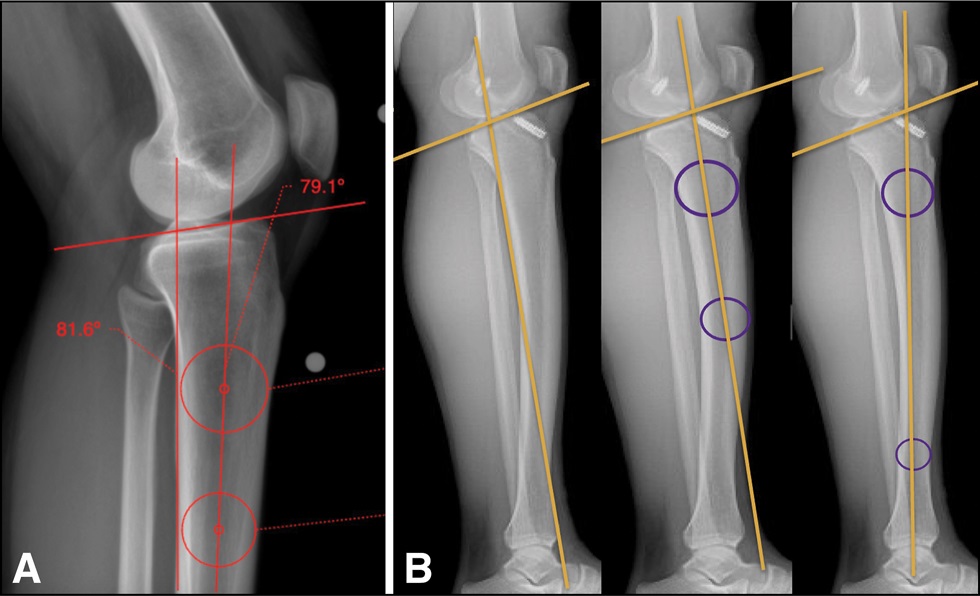

AAOS Appropriate Use Criteria: Case Study on Return to Play to Pre-Injury 2 Level Following Anterior Cruciate Ligament Injury bit.ly/4eo6Gmu Dr. Richard Ma, MD